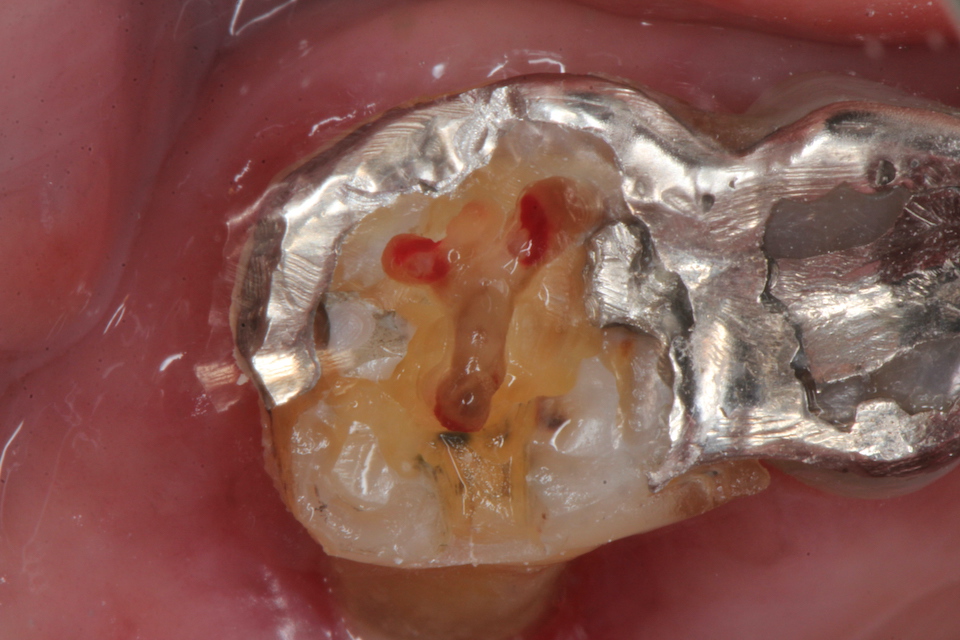

ということで、歯髄は死にかけているな。。と思って天蓋を除去してみた。

天蓋を穿通した。少し出血している。死にかかっている歯に麻酔は要らない。麻酔とは健全な痛みを感じる歯を削る時に必要なだけだ。麻酔が必要な歯を削るということは僕に言わせれば、過剰診療と言っても良い。

上顎6の根管は3つあるはずだ。探している

口蓋根の出血は少ない。ほとんど失活している